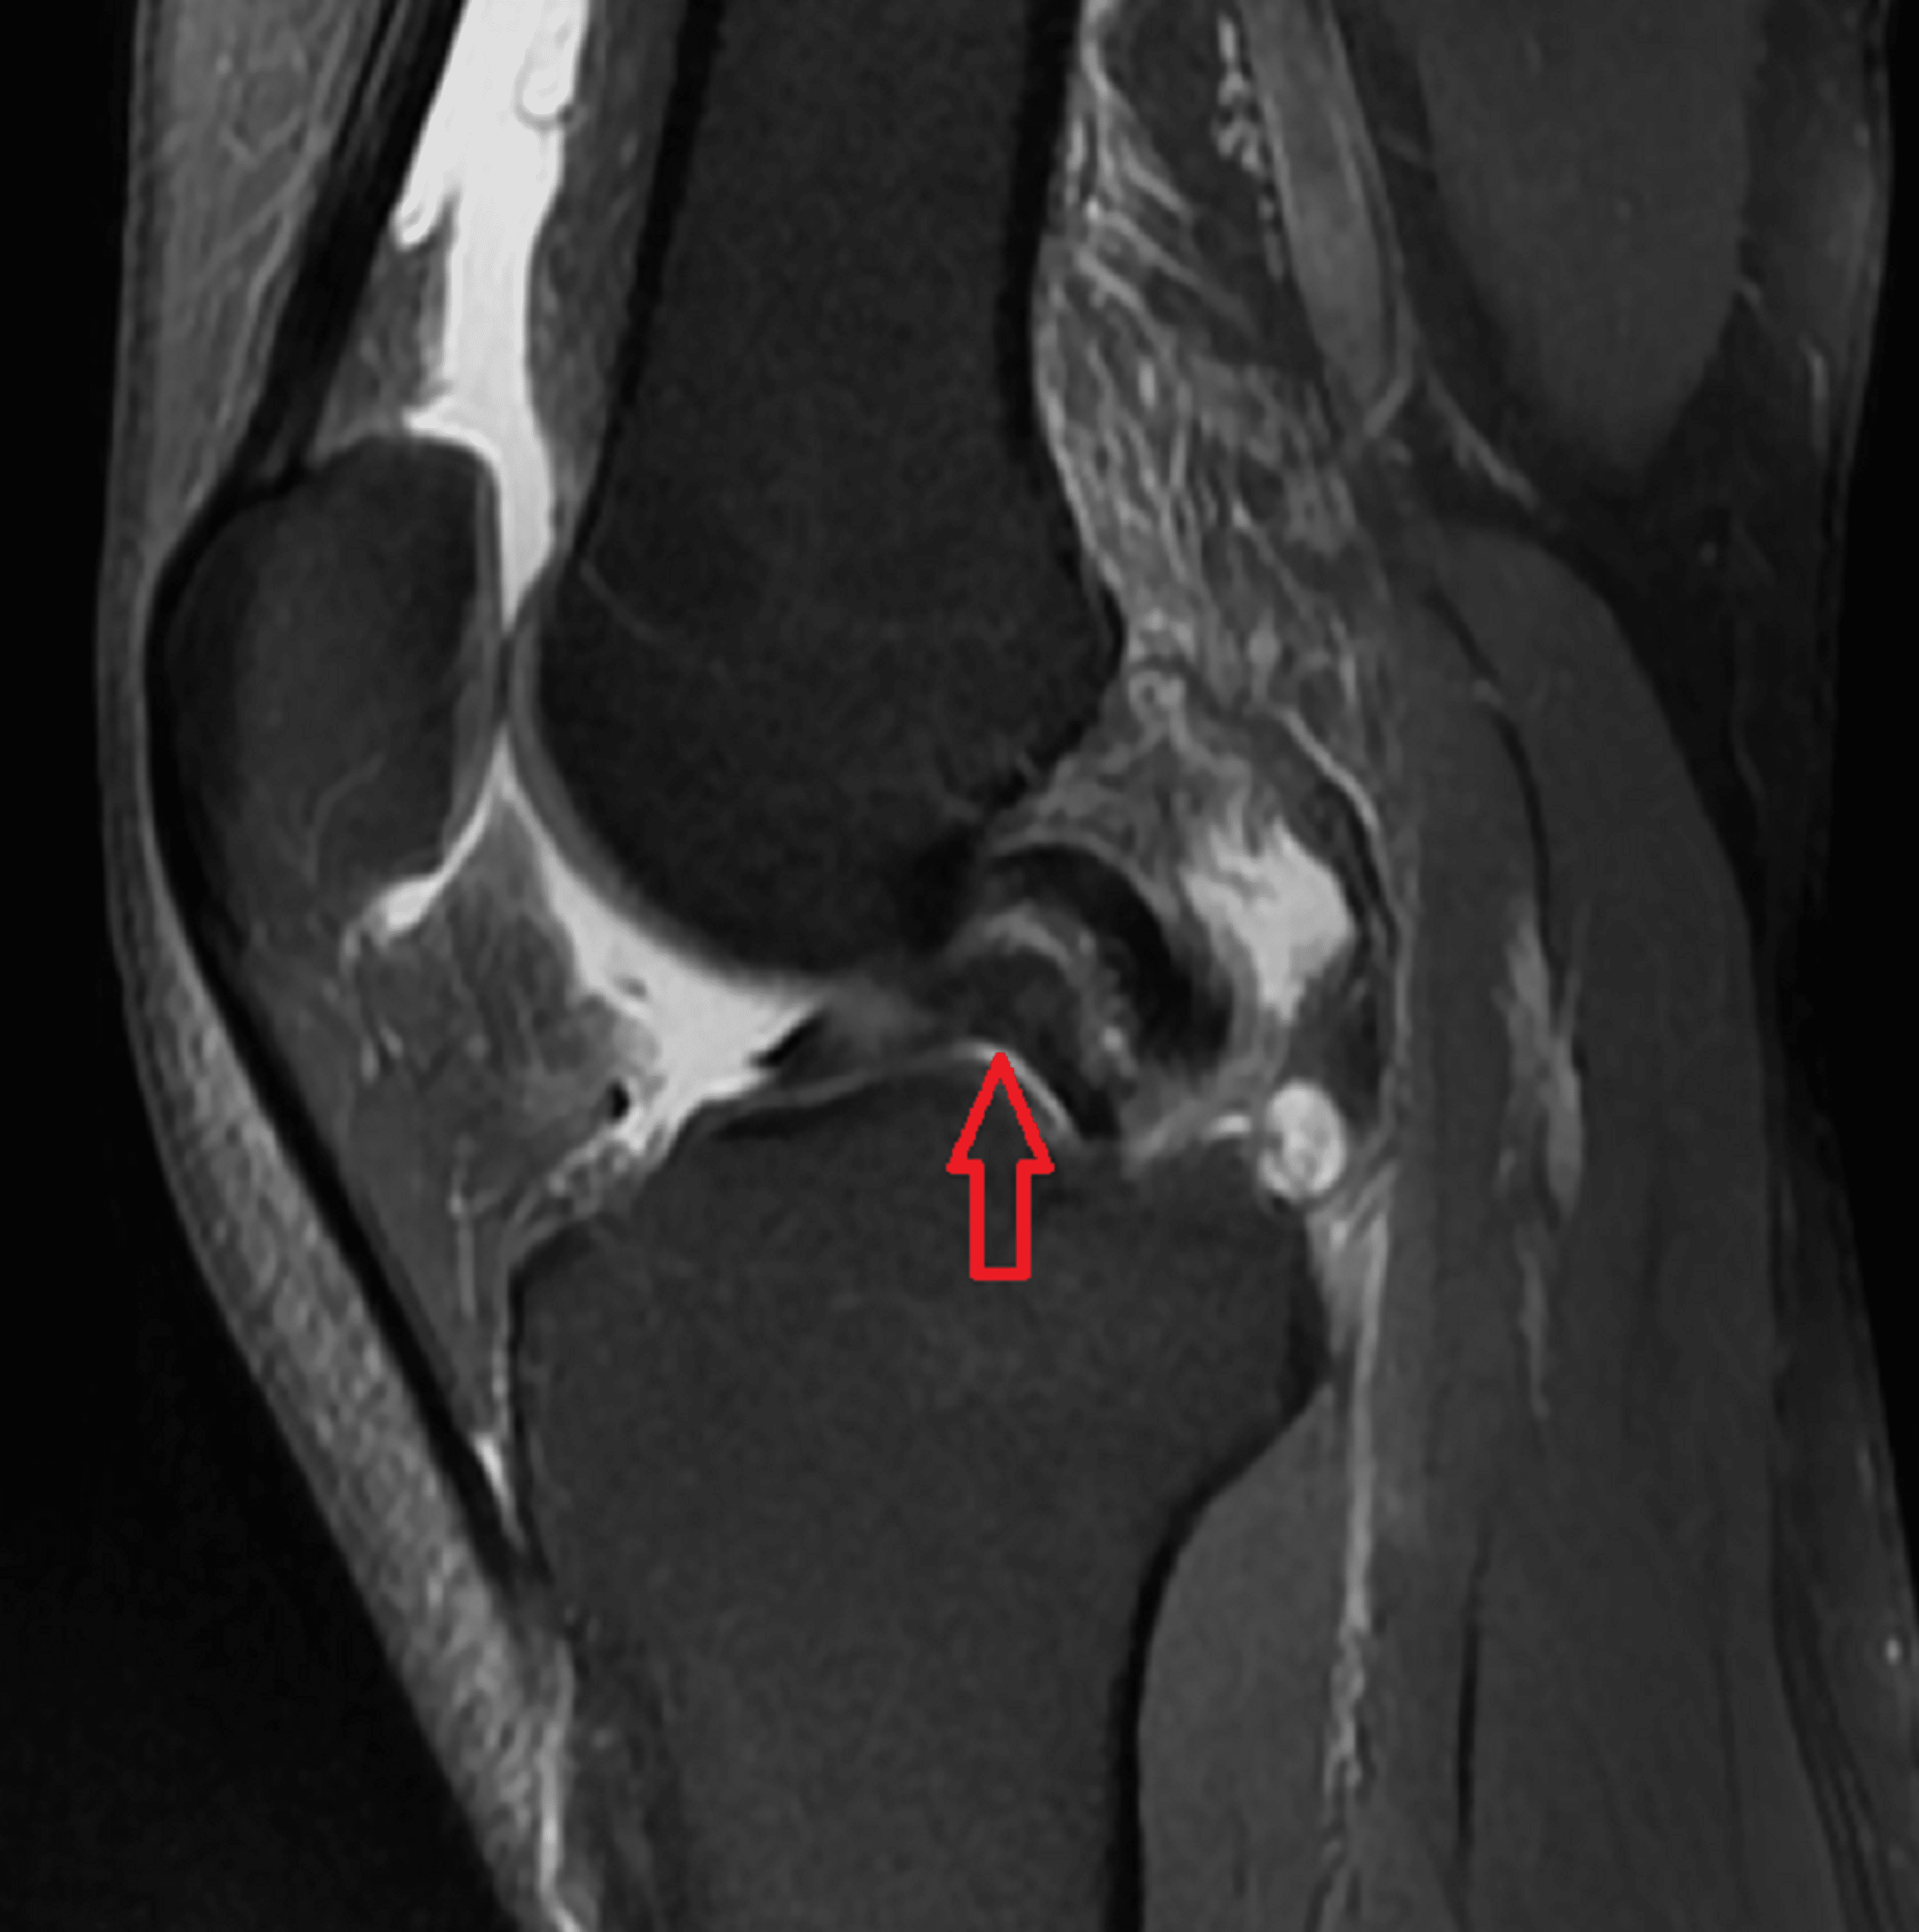

Bucket handle tear with displaced handle in intercondylar notch Radiology Bucket Handle Tear Intercondylar Notch This technique describes repair of a bucket handle tear on the medial meniscus with displacement into the intercondylar notch. They more commonly occur in the medial meniscus. What is a bucket handle meniscus tear? An arthroscopic probe is used for. A bucket handle meniscus tear is a serious injury that results in the meniscus tearing and flipping in the joint.. Bucket Handle Tear Intercondylar Notch.

a Sagittal intermediateweighted MR image with fat suppression depicts Bucket Handle Tear Intercondylar Notch What is a bucket handle meniscus tear? An arthroscopic probe is used for. They more commonly occur in the medial meniscus. This technique describes repair of a bucket handle tear on the medial meniscus with displacement into the intercondylar notch. The repairs they performed in 32 patients. A bucket handle meniscus tear is a serious injury that results in the. Bucket Handle Tear Intercondylar Notch.